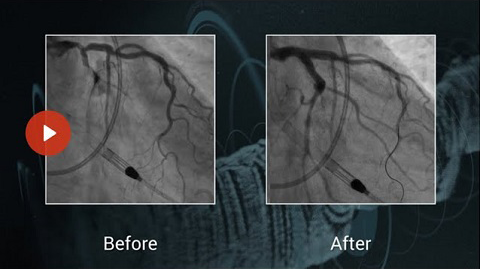

Nodular and eccentric LMS-LAD calcification, treated by rotablation and IVUS guided stenting

Dr. Andrew Ladwiniec presents in this short video how to treat a Nodular and eccentric LMS-LAD calcification using IVUS and rotational atherectomy. You will learn about:

• The utility of rotablation to treat eccentric and nodular calcification

• The importance of adequate lesion preparation to achieve optimal stent expansion in left main stem PCI

• The role of IVUS in identifying fractures in calcification

• The importance of adequate stent expansion to attain good clinical outcomes